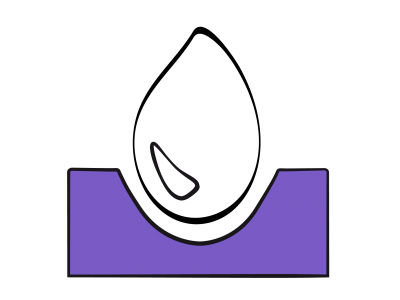

La dysfonction diastolique et la baisse de compliance conduisent à une augmentation des pressions pour le même volume de remplissage et rendent le débit cardiaque davantage dépendant de la précharge, car le ventricule fonctionne sur une courbe de Starling très redressée (Figure 23.5).

Figure 23.5: Relations pression/volume du VG en systole (A) et en diastole (B). A: Courbes de Frank-Starling du VG illustrant la relation entre la précharge et la performance systolique. Courbe normale (en vert), courbe en cas de dysfonction systolique (en rouge), et en cas de dysfonction diastolique (en violet). La courbe de Starling du VD (en pointillé) est très plate, ce qui signifie que le débit du VD normal ne dépend que très peu de la précharge. B : Courbe de compliance normale du VG (en bleu) et lors de dysfonction diastolique (en rouge). Dans ce deuxième cas, une pression de remplissage normale (P) correspond un volume ventriculaire plus petit (V’) que la norme (V) en cas de dysfonction diastolique; le sujet peut être hypovolémique avec une POG (PAPO) normale. La normovolémie d’un sujet souffrant de dysfonction diastolique (V’’ rouge) est une pression de remplissage (P’) qui correspond à une hypervolémie (V’’ bleu) chez un sujet normal.